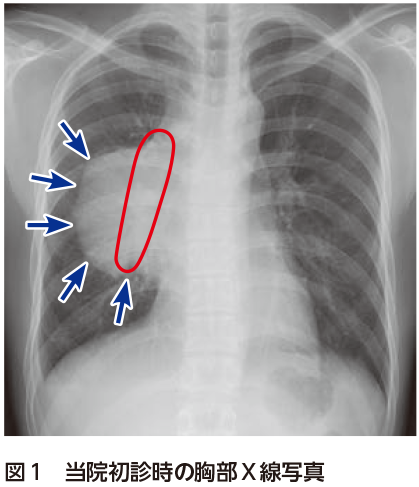

解答 解説 微熱 倦怠感 吸気時の胸痛を主訴に受診した歳代男性 実践 画像診断q A 羊土社 レジデントノート 羊土社